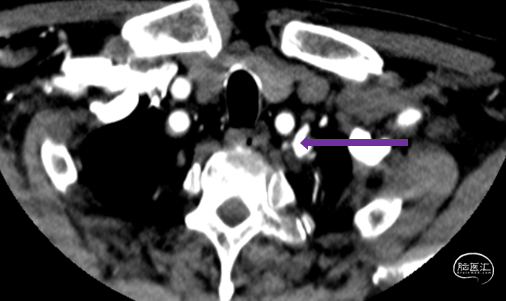

DSA:LSub。

DSA:L-CCA。

0.018*300cm 外周导丝至左肱动脉,0.014*200cm 通桥北斗SS™神经血管导丝超选至左椎V2段远端。

沿0.018*300cm 外周导丝送入6*40 外周球囊送至左侧锁骨下动脉狭窄处,压力泵逐渐加压到6atm。

撤出球囊后见残余狭窄40%。

再次沿0.018*300cm 外周导丝送入6*40 外周球囊达LSub狭窄部位,压力泵逐渐加压到8atm,见残余狭窄20%。